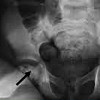

Рентгенография тазобедренных суставов ребенка проводится в детской травматологии и ортопедии, чтобы исключить дисплазию тазобедренного сустава: врожденный до-социальный вывих, подвывих, вывих и рентгенологически незрелые суставы. Как правило, рентгенография тазобедренных суставов ребенка проводится не раньше, чем в возрасте 3 месяцев; до этого ультразвук является предпочтительным. При считывании рентгеновских изображений используются специальные схемы, учитывающие возрастные характеристики костной системы ребенка (схема Рейнберга, Омбредана, Кальве и Шентона, Хильгенрейн). Для исследования тазобедренных суставов используются прямые переднезадние и боковые проекции. Обязательным техническим требованием для исследования является строгая защита половых желез ребенка с помощью свинцовой чаши.